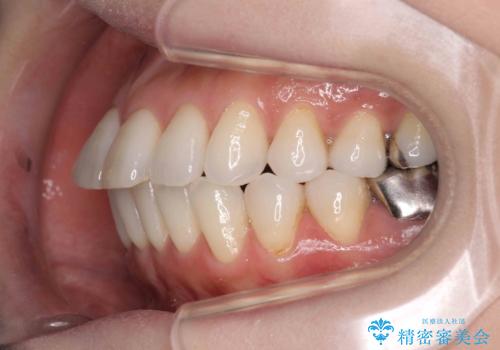

抜歯をせず前歯の角度を改善するマウスピース矯正治療

- 突き出た前歯の角度を改善したい、と矯正治療を希望され来院されました。

抜歯を行いワイヤー矯正で2-3年程度の時間をかけて、しっかり前歯を後方に移動させるか、

抜歯を行わずにIPR(歯の間に空隙を設ける)で可及的に角度の改善を行うか、

2通りの治療方針をご提案しました。

治療期間が約半年で行うことができ、歯を抜かずにマウスピース矯正で可及的に前歯の角度を改善する治療方針を

奥歯の状態等も鑑みて選択されました。

約半年で大きく前歯の角度を改善することができ、抜歯を行わない矯正治療の結果に大変喜んでいただくことができました。